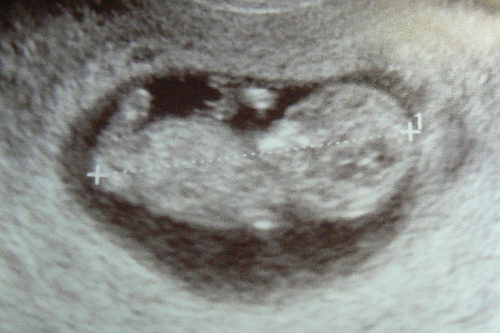

Szóval aznap már hajnalban fent voltam kb. 4 órakor, elkezdtem készülődni, hiszen 6-kor indulnunk kellett itthonról. 3/4 7-re értünk a kórházba, ahol bejelentkeztem a szülőszobán, és azonnal mehettem is be, rámtették a ctg-t, miközben töltötték a papírokat. Igazából fájástevékenységem nem volt, a csajok szívverése viszont teljesen megfelelt. Miután végeztünk, bejöhetett a párom is. Majd a szülésznő előkészített egy szobában a műtéthez, bekötötte az infúziót és vártunk. Befutott a dokim is, mondta hogy mi leszünk az elsők, olyan fél 9 körül kezdünk. 8.20-kor be is toltak a műtőbe, de ott még kb. 10 percig vártam letakarva az anesztesre. Fél 9 után megkaptam a gerincérzéstelenítést, amit meg sem éreztem, pedig nagyon féltem tőle.

Feszítéséket, rángatásokat éreztem, közben a kezemet fogó asszisztens „tudósította” az eseményeket, és mondta, hogy az első baba mindjárt kint van. Aztán hallottam ahogy Zsani felsír, láttam a kis lila testét, a szülésznő pedig mondta hogy ez a baba becslése szerint több mint 3 kg, majd bevitte orvosi ellenőrzésre. Rögtön utána meghallottam a második sírást is, és Blanka kis lila testét. Pár perc múlva hozták őket, mindketten szépen csendben pihiztek a szülésznők kezében, megsimíthattam, megpuszilhattam őket.

Elvitték őket az apukájukhoz, közben engem összevarrtak, akkorra borzasztóan fáztam. 3/4 10-kor toltak ki a műtőből a szobámba, ahol kb. még másfél óra kellett mire a hidegrázás elmúlt. Délután a párom már behozhatta őket a szobámba. Szinte hihetetlennek tűnt, hogy ez a két kis tünemény hogyan fért el a pocimban. Láttam a sima kis arcocskájukat, békésen alukáltak. Anya lettem, azóta is imádom őket!